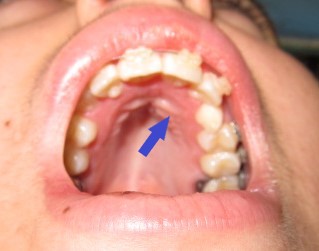

- ΑΠΟΚΑΛΥΨΗ ΤΟΥ ΕΓΚΛΕΙΣΤΟΥ ΚΥΝΟΔΟΝΤΑ ΚΑΙ ΑΜΕΣΗ ΤΟΠΟΘΕΤΗΣΗ ΤΟΥ BRACKET ΑΠΟ ΤΟΝ ΟΡΘΟΔΟΝΤΙΚΟ.

ΧΕΙΡΟΥΡΓΙΚΗ ΑΠΟΚΑΛΥΨΗ ΚΑΙ ΑΜΕΣΗ ΤΟΠΟΘΕΤΗΣΗ BRACKET ΣΕ ΕΓΚΛΕΙΣΤΟ ΚΥΝΟΔΟΝΤΑ ΑΝΩ ΓΝΑΘΟΥ ΣΤΗΝ ΑΡΙΣΤΕΡΗ ΠΛΕΥΡΑ ΤΗΣ ΑΣΘΕΝΟΥΣ.